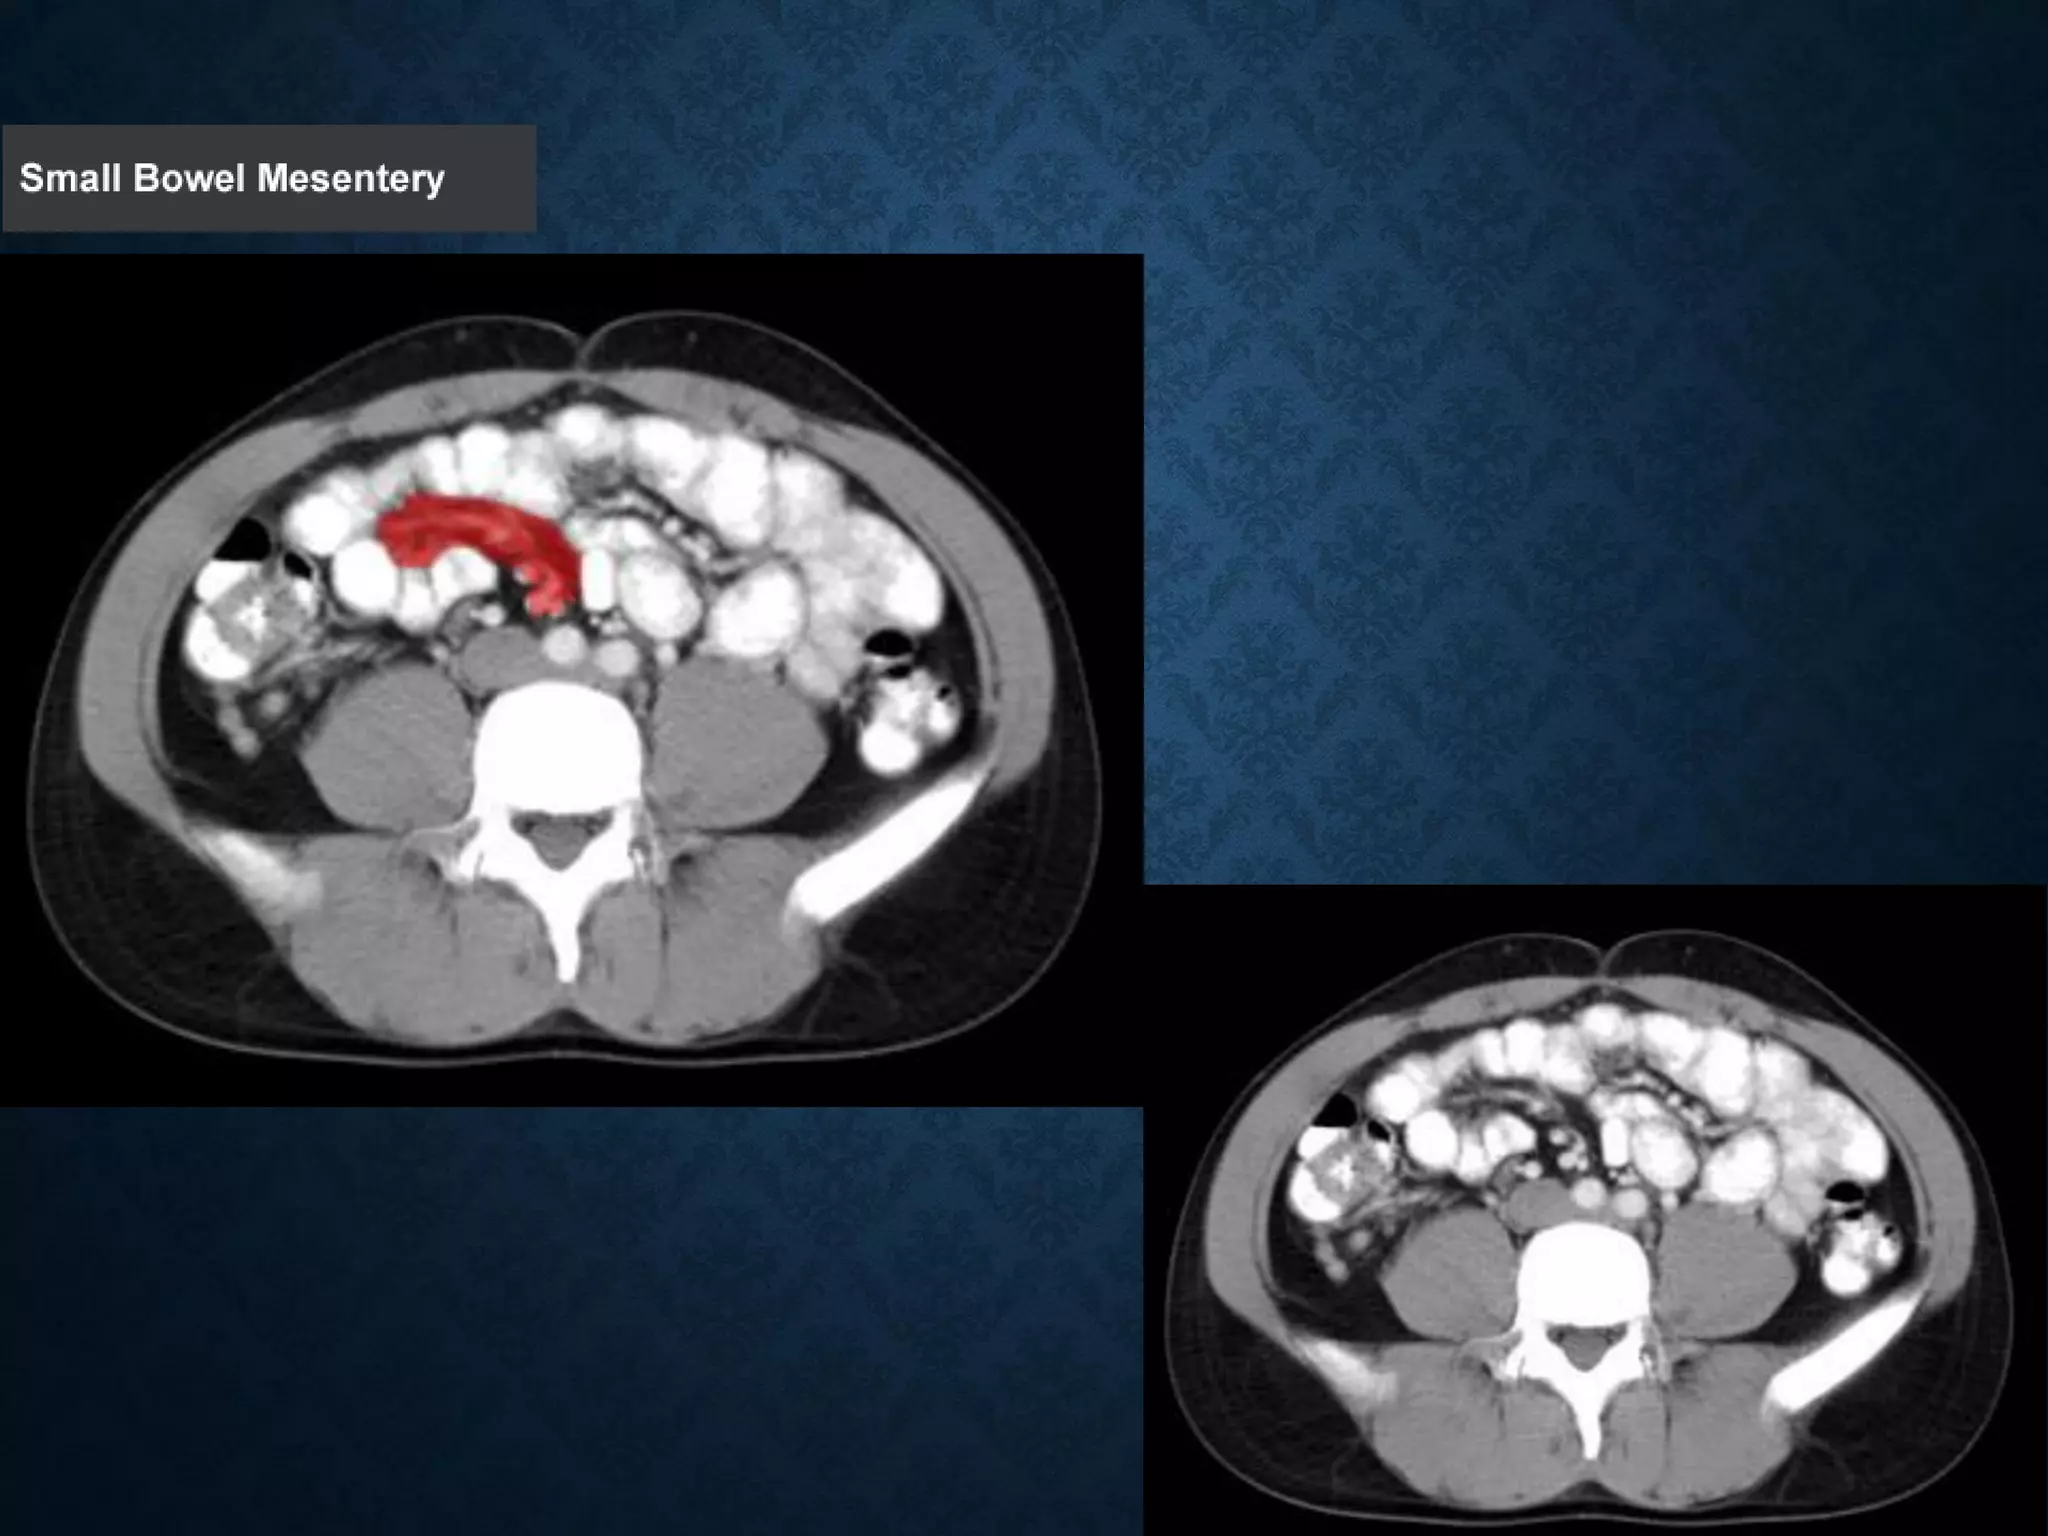

Identify the following structures in the body CT to the right. To view the location of the structure in the image click on

the label at the left and the structure will be indicated in the image. Abdominal CT scans typically begin just above

the diaphragm, so the first slice you see is of the lower chest.